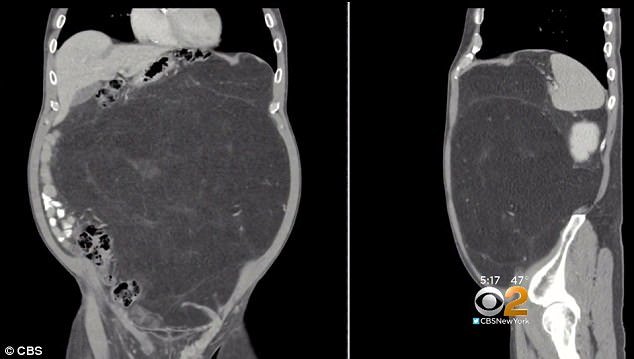

Lúc này, các bác sĩ mới phát hiện một khối u trong bụng Daly và kết luận ông bị liposarcoma, một dạng ung thư phát triển trong tế bào mỡ của các mô mềm.

Các chuyên gia y tế tin rằng khối u đã xuất hiện trong bụng ông Daly khoảng 10 - 15 năm mới có thể lớn như thế. Ngoài ra, Daly cũng may mắn khi khối u chưa gây cản trở gì tới chức năng hoạt động của các bộ phận trong cơ thể.

Trong lúc mổ, các bác sĩ phát hiện ra khối u lớn gần gấp ba lần kích thước dự đoán ban đầu. Đây là khối u khổng lồ nằm ở vùng bụng và bao quanh một quả thận của ông.

"Nhìn trên ảnh là một chuyện, đến khi cầm khối u trên tay lại là chuyện khác", Julio Teixeira, bác sĩ phẫu thuật của ông Daly, nói.

Khối u nặng 13,6 kg và là khối u lớn nhất mà các bác sĩ ở Bệnh viện Lenox Hill từng tiến hành phẫu thuật cắt bỏ. Các bác sĩ cho hay nếu như ông Daly không phát hiện sớm, thì có thể chỉ sống được khoảng vài tháng nữa